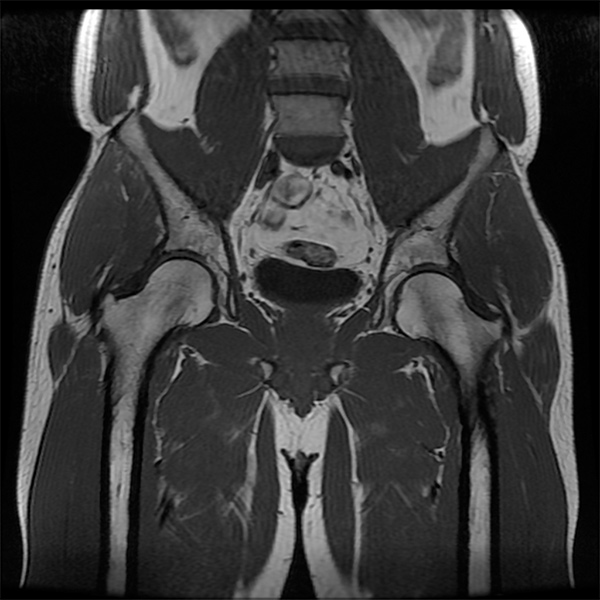

- Imaging of Abductor Tears: Stepwise Technique for Accurate Diagnosis

- Radiographic Risk Factors and Signs of Abductor Tears in the Hip

- Prevalence of Gluteus Medius Pathology on MRI in Patients Undergoing Hip Arthroscopy for Femoroacetabular Impingement: Asymptomatic Tears Are Rare, Whereas Tendinosis Is Common

- Clinical Presentation and Imaging Results of Patients With Symptomatic Gluteus Medius Tears